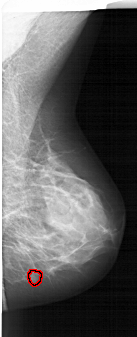

A_1877_1.LEFT_MLO

LEFT_MLO LINES 6481 PIXELS_PER_LINE 3061 BITS_PER_PIXEL 12 RESOLUTION 43.5 NON_OVERLAY

FILE: A_1877_1.RIGHT_MLO.OVERLAY

TOTAL_ABNORMALITIES 1

ABNORMALITY 1

LESION_TYPE MASS SHAPE LOBULATED MARGINS CIRCUMSCRIBED

ASSESSMENT 4

SUBTLETY 3

PATHOLOGY BENIGN

TOTAL_OUTLINES 1

BOUNDARY